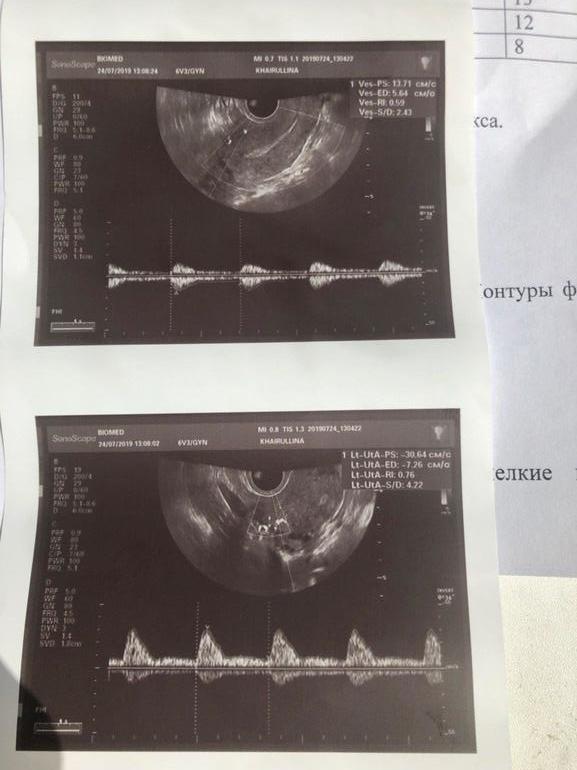

сегодня у другого врача в другой клинике 7,8......(((ну и сам доплер, помогите пожалуйста, разобраться , узист делала молча, в заключении ничего нет

1.Правая маточная артерия 2.Левая маточная артерия 3.Аркуатные артерии 4.Радиальные артерии 5.Базальные артерии 6.Спиральные артерии Наиболее важные для имплантации и вынашивания на первоначальном этапе и наиболее часто страдающие от ХЭ артерии - это Базальные и Спиральные. Пока кровотока в них нет, или он снижен, беременность может продолжать срываться/замирать. Правая и левая маточные артерии не столь важны для вынашивания на первоначальном этапе. Однако обычно с ними как раз у большинства все в порядке. Во время измерения сосудов, на экране монитора будут ловить пульсацию в каждой артерии, и вы будете видеть примерно такую картинку: УЗИст же будет замерять эту пульсацию. Это правильное исследование. Часто доплером называют еще вот этот "режим цветных пятен": Это тоже кровотоки в режиме доплера. Многие УЗИсты просто смотрят именно этот режим доплера и сообщают вам, что все хорошо. Не ведитесь! Информации о скорости кровотоков такое исследование не несет. Когда делать доплер? Доплер сосудов матки необходимо делать на 5-7 ДПО (день после овуляции). Нормы доплера есть на любой день цикла, и в принципе узнать о плохом кровотоке вы можете, сходив на доплер в любой ДЦ. На 5-7 ДПО его смотрят за тем, что это время приходится на окно имплантации при возможной беременности. Какой нужно получить результат от УЗИста на руки? Правильный результат доплера выглядит как все перечисленные выше артерии с количественными показателями, включая самый популярный - Индекс Резистентности (ИР). (Или только с ИР, этого достаточно). Если по-английски, то RI. Данный индекс характеризует скорость кровотока и имеет свои нормы. Резистентность - это сопротивление, то есть чем ИР ниже, тем лучше, тем быстрее кровоток, а значит лучше для беременности. То есть когда говорят о высокорезистентном кровотоке, имеют ввиду, что кровоток плохой. Соответственно, на руки вам должны выдать результат ИР во всех шести артериях матки и вывод УЗИста о состоянии кровотока. Каковы нормы доплера? Нормы ИР для второй фазы цикла:

1.Правая маточная артерия 0,71-0,90

2.Левая маточная артерия 0,72-0,91

3.Аркуатные артерии 0,70-0,80

4.Радиальные артерии 0,60-0,72

5.Базальные артерии 0,50-0,57

6.Спиральные артерии 0,45-0,52

(Взято из научного труда) Некий профессор М.Н. Буланов разместил в интернете вот такие нормы на основании собственных данных. (Смотрим строку 19-23). У него нет норм базальных, спиральные такие же, для остальных артерий более строгие верхние границы: Большинство доплеров, что я видела, опираются на нормы, совпадающие с этой таблицей. Нормы по клиникам могут отличаться. Но незначительно (на сотые доли). В любом случае УЗИст должен вам написать, где у вас норма, а где нет. Как интерпретировать результаты доплера? Если значение ИР по любой артерии у вас НИЖЕ нормы, то это даже хорошо! Если значение ИР по любой артерии ВЫШЕ нормы, либо указано, что в какой-то артерии "кровоток не регистрируется", то такой доплер плохой: кровоток снижен и требуется его "разгон" физиотерапией. Если УЗИст не замерил вам все шесть артерий, такой доплер нельзя считать "хорошим", так как полной картины кровотока нет и вы не знаете, что у вас с кровотоком на самом деле. Если УЗИст вообще не замерял артерии, а просто сказал, что все хорошо. То тут тоже стоит засомневаться, замерил ли он он что-то вообще. Все другие артерии типа "интраоваривальной" или кровоток около желтого тела, не имеют значения в плане влияния на поверхность матки. Если доплер хороший? Если доплер хороший, значит ХЭ вынашиванию не помешает (при условии устранения остальных сопутствующих ему факторов). Подробнее тут. Что делать, если доплер плохой? Разгонять кровоток физиотерапией до получения хороших результатов доплера. Иногда требуется не один курс. Подробнее о физиотерапии тут. Но может быть есть исключения, когда не надо делать физио при плохом доплере? Исключение только одно - если Б наступает, но закачивается все время ЗБ, то есть имплантация все же происходит, то теоретически можно вытянуть на капельницах Актовегина с ХГЧ 1000. Однако это рискованно, и так как кровоток плохой, то возможно продолжение неудач.